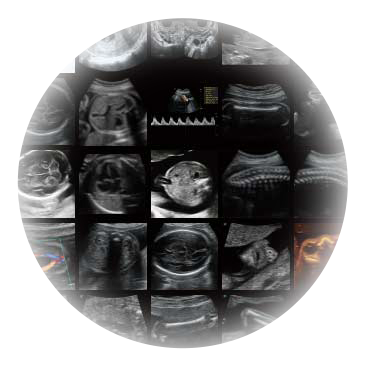

自动获取标准切面,自动完成测量,帮助医生快速完成检查,同时提升测量准确性。

宽频带腹部凸阵探头和腹部容积探头、大角度腔内探头和腔内容积探头、独特的生殖专用曲柄探头,为妇产应用提供全面诊疗方案。